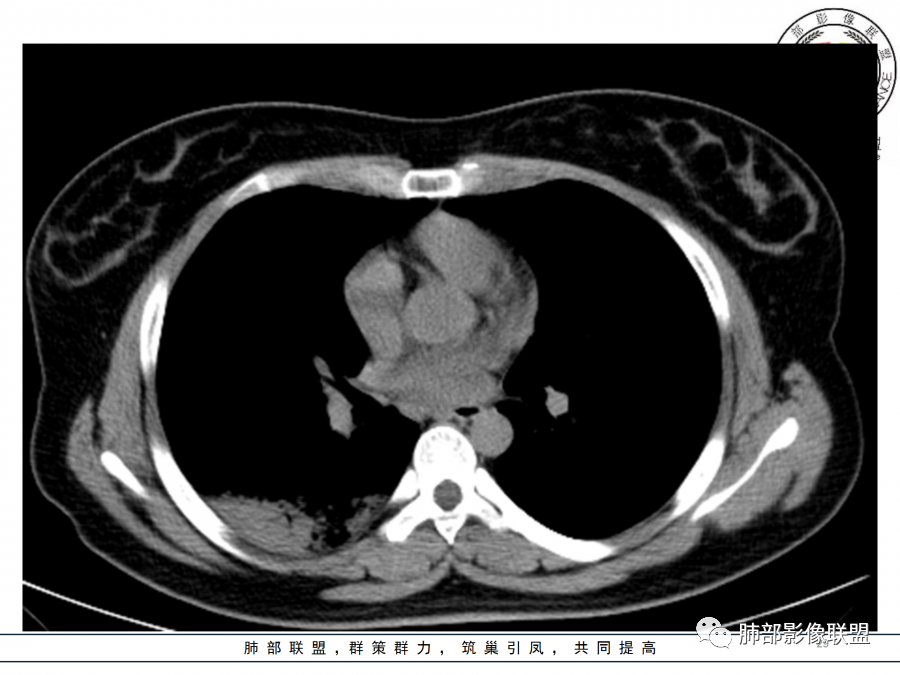

右肺胸膜下实变,病变跨多个叶生长,宽基底与胸膜相连,近端支气管穿行病灶内,并可见片状磨玻璃影,边界清,部分远端小支气管堵塞,支气管略有扩张,周围散发小结节,临床年轻女性,炎性指标高,发热六日,首先考虑感染性病变(肺链,奴卡,隐球,OP)鉴别淋巴瘤。

年轻女性,无明显诱因发热,体温略高,起病较急,有畏寒,右下肺紧贴胸膜下片状实变影,部分融合,外围有结节影,性质比较单一,类似于蘑菇兄弟,病灶周围伴有晕,支气管进入近端扩张远端堵塞,常规考虑感染,肺炎链球菌、隐球菌。

青年女性,发热咳嗽5天,炎症标志物升高。右肺下叶大片实变伴周围GGO,GGO内未见细网格,主体与胸膜平行,似多个病灶融合,实变区内见支气管部分进入,部分支气管受压狭窄,周围可见多发卫星病灶。支持炎性,考虑隐球感染,鉴别op。

年轻女性,急性起病,咳嗽,发热,黄痰,白细胞高,CRP基本正常,基础体健。CT提示右肺下叶实变,宽基底与胸膜相连,长轴平行于胸膜,可见支气管充气征,于病变中央截断,走形自然,胸膜下脂肪间隙可见,倾向于隐球菌,鉴别肺链,军团菌等。

右肺胸膜下实变,病变跨多个叶生长,相互融合,宽基底与胸膜相连,支气管气象,并可见片状磨玻璃影,边界清,炎性指标高,发热六日,考虑感染病变,链球菌?腺病毒待排。

26岁,女性,发热、咳嗽5天。咳少量黄痰,起病急,病程短,白细胞及中性高,血沉及D-二聚体增高。胸部CT:右肺下叶大片实变,长轴沿胸膜分布,宽基底与胸膜接触,边界不清,周围GGO,部分团片影融合,病灶内可见支气管充气征,部分支气管进入病灶后阻塞。考虑:感染性病变,隐球菌?脓毒肺栓塞?鉴别:肺炎型肺Ca。

1.年轻女性,咳嗽、发热(38.8°),起病急,血象高。影像上大片实变影为主,一般会首先考虑细菌性肺炎,尤其是肺炎链球菌感染等。疗效不满意时考虑其他。

2.影像上怀疑其他病灶的理由有:

1)实变影为大小不等多中心性。

2)沿胸膜下分布趋势(不同于大叶性肺炎的肺叶“造型”)。

3)周围较大范围磨玻璃影及小叶间隔增厚。

4)病灶体积增大明显(叶间裂推移)。

3.腺病毒肺炎可以符合上述改变:实性密度,间质分布为主等。

4.隐球菌感染可以符合上述改变:胸膜下多中心实变密度为主,磨玻璃晕等。但隐球菌临床症状大多隐匿、迁延,影像变化缓慢。

5.本例患者血象高,影像渗出明显,尚不能排除混合感染可能。